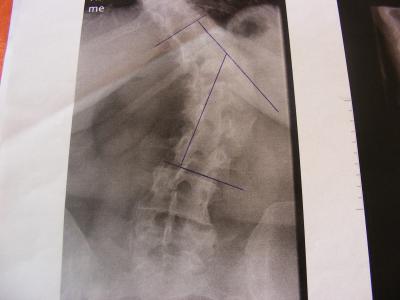

Nun habe ich konkrete neue und hoffentlich dann auch richtige Zahlen (ich kann auch nur die Zahlen angeben - welche ich von den jeweiligen "Orthopäden" bekomme) vom Grad der Krümmungen - ich hatte zu dem Zeitpunkt als ich mich angemeldet habe einen anderen Arzt mit dem ich nicht zufrieden war (was ich ja hier häufiger gelesen habe) und habe gewechselt, von dem Orthopäden hatte ich die Angaben in meiner Anmeldung, dann kam Orthopäde Nr.2 welcher mich gern auf der Schlachtbank gesehen hätte - heute nun Orthopäde Nr. 3 und bekam diese Angaben: Krümmung oben 63° Krümmung unten 56° dazu eine schwere Arthrose in der linken Schulter welche dort die starken Schmerzen verursacht! Ein Korrekturkorsett ist nicht mehr machbar, soll mit KG nach Schroth anfangen für die Krümmung BWS, jetzt habe ich erst einmal KG für die Arthrose in der Schulter bekommen, in der LWS hat sich die WS von selbst angefangen zu versteifen, daher auch die Aussage das ich kein Korsett mehr bekommen kann! Ich werd die Bilder mal abfotografieren und dann kann sich jeder mal selbst ein Bild davon machen!

So hier noch zwei Bilder....

Ich würde dir dennoch die Meinung eines Skoliose-Spezialisten empfehlen, der erstens die Korsettfrage klären kann und zweitens auch mal ordentliche Bilder von der Wirbelsäule macht, deine Bilder sind leider Teilaufnahmen.